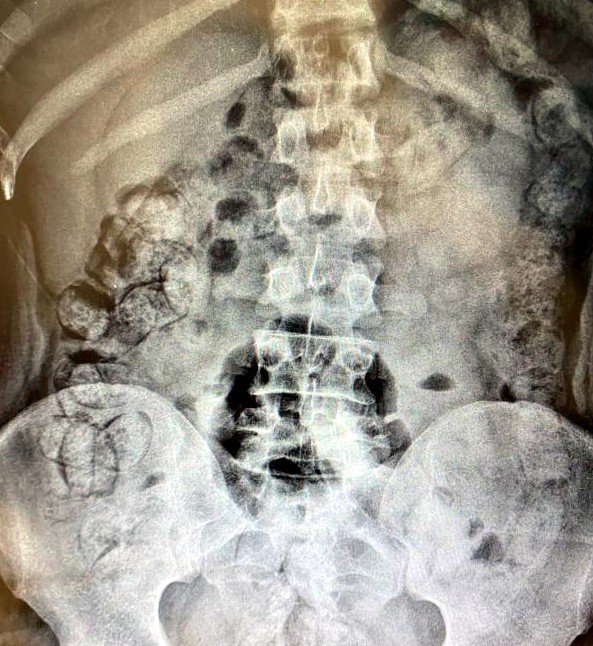

Alınan bilgiye göre, Erzincan Emniyet Müdürlüğü Narkotik Suçlarla Mücadele Şube Müdürlüğü ve KOM şube ekiplerince geçtiğimiz 28 Mart 2023 günü İran plakalı yolcu otobüsü uygulama noktasında durduruldu. Otobüste yolcu olarak bulunan Khadijah S., ve Samira T., isimli şahıslar ile aynı otobüste bağlantılı oldukları tespit edilen Allahniaz S., Raheleh Y., isimli İran uyruklu 4 şahsın yapılan iç beden muayenelerinde, yutma suretiyle uyuşturucu kuryeliği yaptıkları belirlendi. Şüpheli Khadijah S., isimli şahıstan 31 parça halinde yaklaşık ağırlığı 252,52 gram Afyon sakızı, Samira T., isimli şahıstan 64 parça halinde 440,78 gram, toplam 693,3 gram Afyon sakızı ele geçirildi.